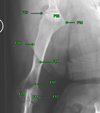

1

Q

F2

A

Body of scapula

2

Q

F3

A

Angles of Scapula

3

Q

What is F4?

A

Spine of Scapula

4

Q

What is F5?

A

Acromion process

5

Q

What is F6?

A

Glenoid Fossa

6

Q

What is F7?

A

Supraglenoid tubercle

7

Q

What is F8a?

A

infraspinatus fossa

8

Q

What is F8b?

A

supraspinatus fossa

9

Q

F10

A

Head of Humerus

10

Q

F11

A

condyles of humerus

11

Q

F12

A

Epicondyles of humerus

12

Q

F13

A

greater tubercle of humerus

13

Q

F14

A

lesser tubercle of humerus

14

Q

F16

A

deltoid tuberosity of humerus

15

Q

F17

A

supratrochlear foramen

16

Q

F19

A

nutrient foramen of humerus

17

Q

F15

A

intertubercular groove of humerus

18

Q

F18

A

supracondylar foramen of humerus